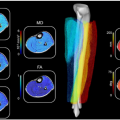

L'architecture des muscles explorée par IRM à très haut champ

Vie et Terre